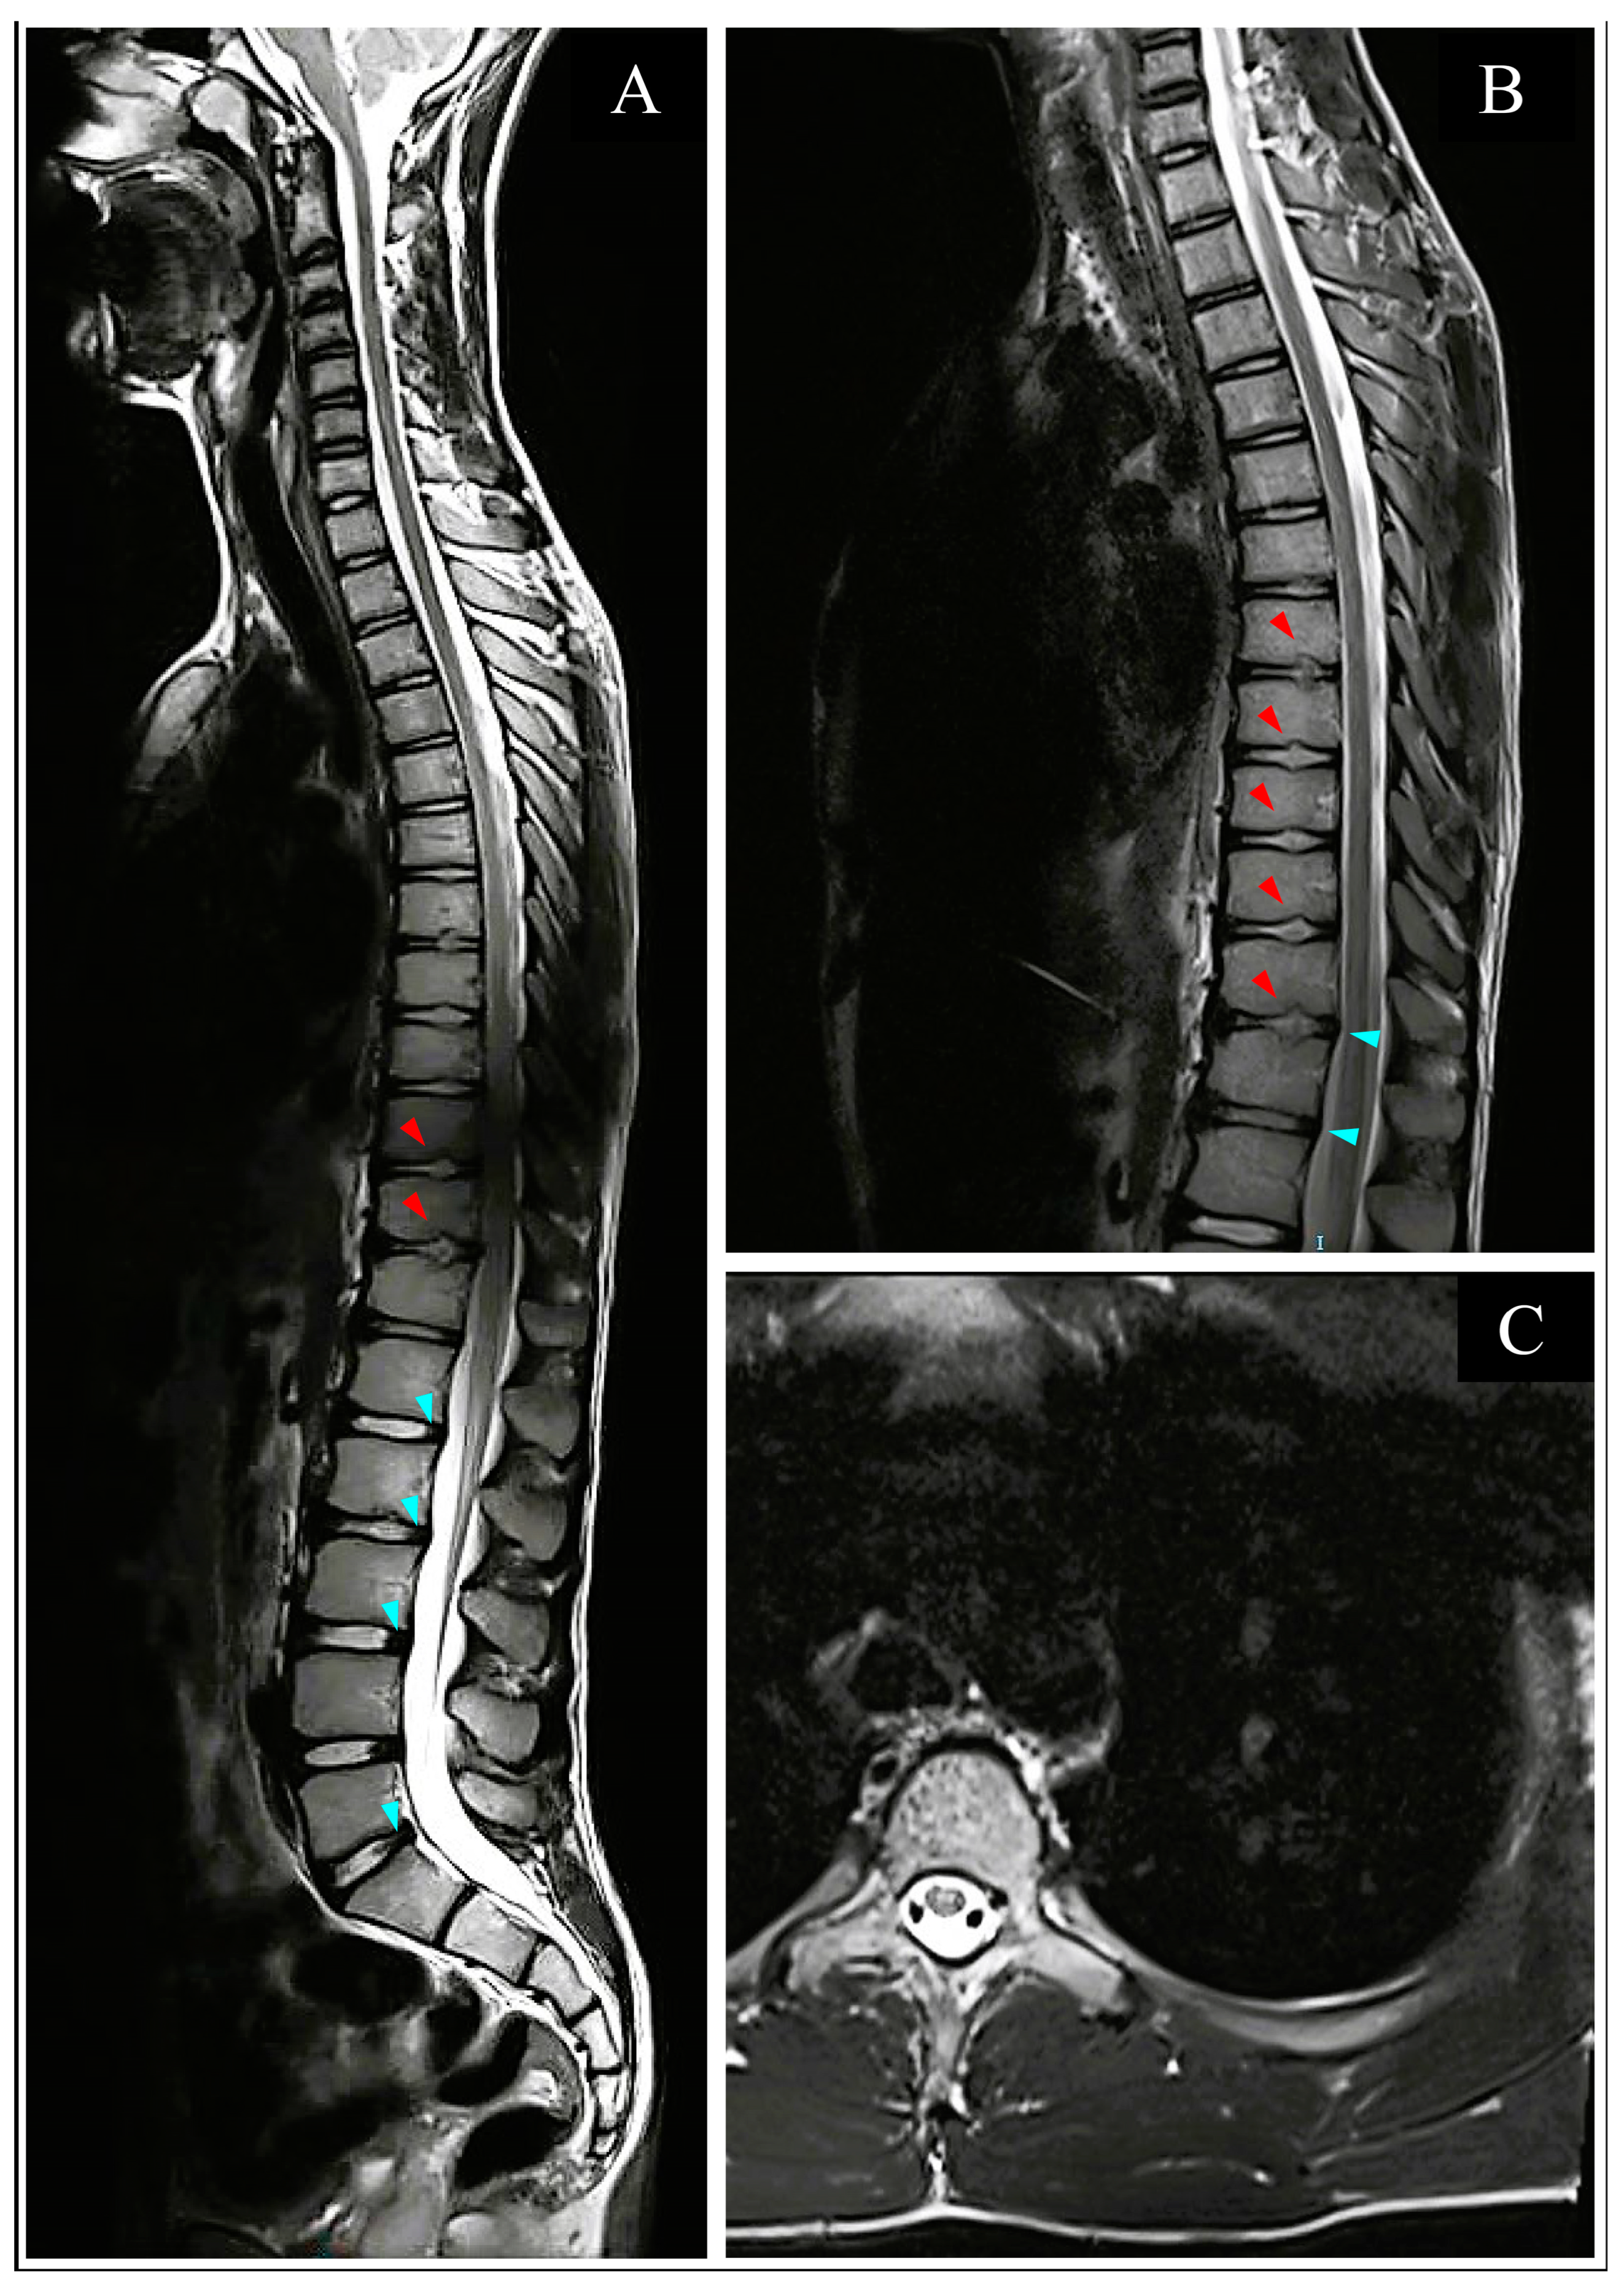

3.3.2. Imaging